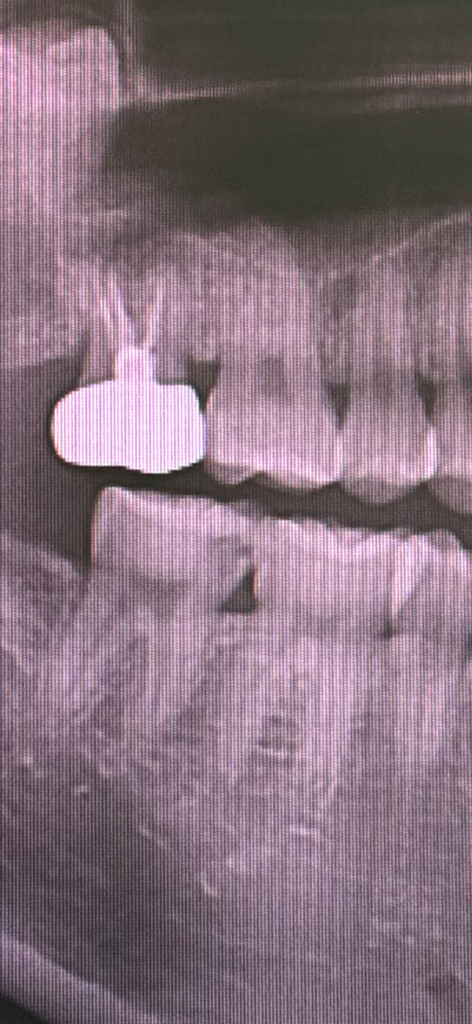

사진상으로는 치료가 필요한 치아이며 인레이치료를 해야할 것으로 보입니다.

충치가 멈췄다기엔 진행이 너무 많이 되었습니다.

치아 사이에 충치가 굉장히 심하신거 같습니다. 저정도 충치라면 신경치료를 해야될 가능성이 높아 보입니다.

정지우식이라 할지라도 방사선사진상에서 저정도로 보인다면 이미 치아(치질)가 파괴된 것이 옆쪽으로 보일 정도로 추정됩니다

가능하면 치료를 해주는 것이 더 심한 치아 파괴를 막는데 좋을 것 같습니다